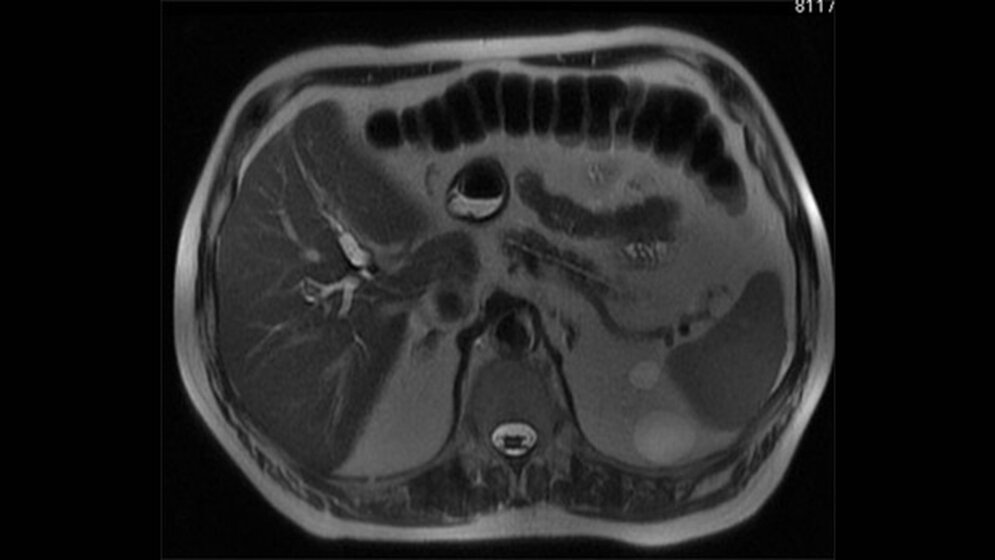

Der Artikel stellt die meist enutzten Sequenzen, deren Aufbau und Funktion vor. Bevor wir uns aber mit den Sequenzen beschäftigen, wiederholen wir kurz die Grundlagen.